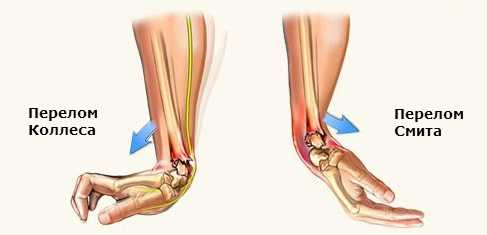

- Травма Коллиса – разгибаемый перелом кости. Обусловлен падением на открытую ладонь.

- Перелом Смита – сгибательная травма. Кость запястья ломается при приземлении на тыльную часть.

- Перелом Коллеса (разгибательный). Возникает в результате падения на открытую ладонь или сильного удара по открытой ладони. В этой ситуации костные отломки отходят в направлении от ладони. Восстановление идет быстрыми темпами за счет хорошего кровотока.

- Перелом Смита (сгибательный). Связан с ударом (например, неточный, но сильный удар кулаком) или падением на тыльную (оборотную) сторону ладони. Лучевая кость перемещается в направлении ладони, кисть деформируется. Лечение и реабилитация требуют времени и усилий.

- Травма Коллеса. Это разгибательное повреждение, которое происходит после падения на открытую ладошку. Костный фрагмент, который расположен выше смещается к тыльной части предплечья. Впервые травма Колеса была описана Ирландским хирургом Авраамом Коллесом.

- Травма Смита. Это сгибательный перелом, которому предшествует падение на тыльную сторону руки. Во время смещения дистальный фрагмент кости перемещается к наружной части предплечья. Этот случай впервые был описан Робертом Смитом.

- Перелом Смита. Чаще всего он возникает в результате удара прямыми ладонями или падения на вытянутые руки. В этом случае кость повреждается выше ее дистального кольца на несколько сантиметров. При этом обломки кости перемещаются в противоположную от ладони сторону. Благодаря тому, что кровообращение в этой области достаточно активно, травмы быстро срастается;

- Перелом Коллеса. Встречается гораздо реже и возникает в результате падения на спину и прямого удара предплечья. При этом осколки лучевой кости смещаются к ладони.